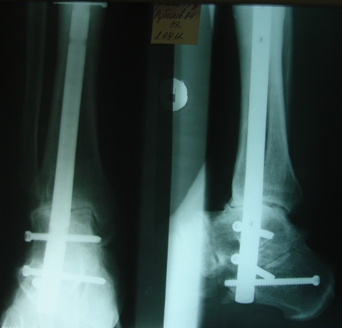

Взаимоисключающие требования, т.к. от боли его из бавит только

артродез, но он, соответственно, лишит движений. В приложении

- малоинвазивный компрессионный артродез с помощью БИОС.

Боли прошли сразу после операции.